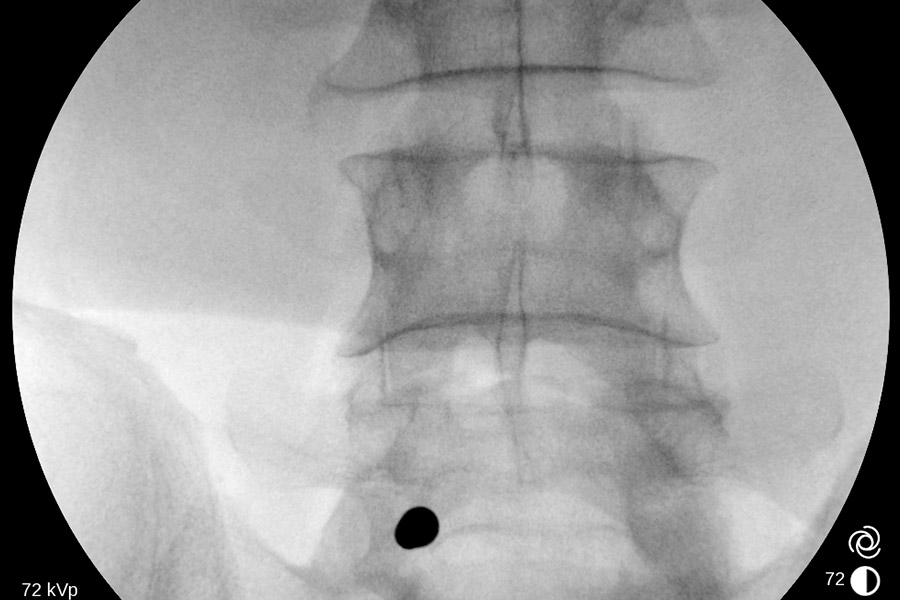

Caso clínico: endoscopia de columna multinivel L4L5 y L5S1

Los síntomas que presentaba el paciente eran dolores acentuados en las piernas, claudicación a la marcha y calambres y hormigueos en las piernas.

Durante la intervención quirúrgica, se abordarán los dos niveles mediante la técnica de endoscopia de columna.